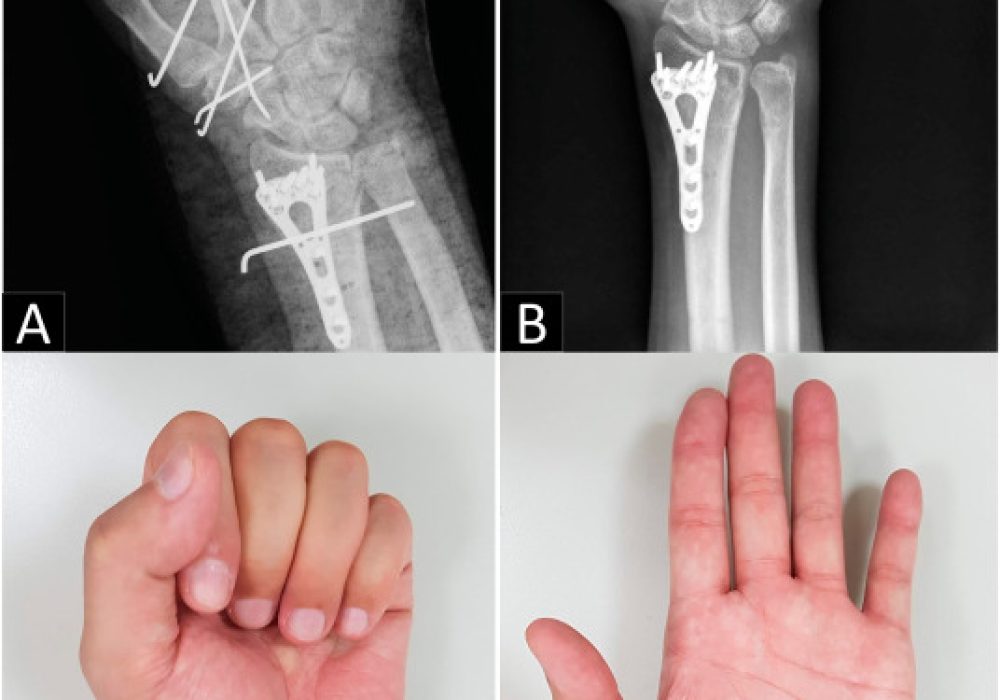

The carpal ligaments are not usually broken or attenuated, but the dorsal tilt of the malunited distal radius and compensatory dinner fork extension of the proximal row reduce the distances between their origins and insertions. Therefore, Soft ligaments are unable to prevent capitate dorsal translation and distal carpal row.

Dorsal Intercalated Segment Instability (DISI)